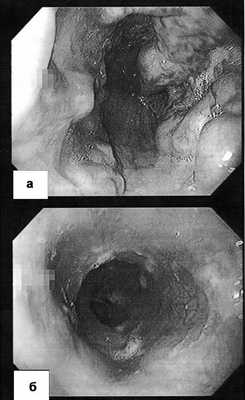

СФГДС от 20.10.13: пищевод: слизистая розовая, блестящая, на уровне средней и нижней трети на всех стенках имеются варикозно-расширенные вены, выступающие в просвет до 0,2—0,3 см, перистальтика сохранена. Слизистая нижней трети пищевода осмотрена в режиме NBI — переходная зона не расширена, Z-линия четкая, слизистая без признаков метаплазии. Желудок: форма правильная, слизистая умеренно диффузно гиперемированная, блестящая, умеренно атрофична, в антральном отделе единичные «полные» в неактивной фазе по 0,2 см точечные геморрагические эрозии. Двенадцатиперстная кишка: луковица правильной формы, слизистая умеренно гиперемированная, блестящая, большой дуоденальный сосочек до 0,3 см, не изменен. Заключение: поверхностный гастродуоденит с эрозиями в антральном отделе. Дуоденогастральный рефлюкс, варикозное расширение вен пищевода I степени (рис. 4).

Рис. 4. Серия снимков, выполненных во время ЭФГДС пациентки Л. через 7 лет после СРВШ. Видны варикозно-расширенные вены пищевода I степени.

Эзофагогастродуоденоскопия. Пищевод свободно проходим, имеются умеренные рубцовые изменения слизистой, варикозное расширение вен нижней трети пищевода до 2 мм, варикозно-расширенные до 5-8 мм вены кардиального отдела желудка с переходом на дно с множественными эрозиями, визуализированы ранее лигированные и склерозированные некротизированные варикозно-расширенные вены без признаков кровотечения, привратник сомкнут, луковица двенадцатиперстной кишки не изменена (рис. 1, а). Рисунок 1. Гастроскопия (а) до операции. Стрелкой указан некротизированный варикс через сутки после лигирования. Объяснения в тексте. Рисунок 1. Гастроскопия (б) после операции. Заключение: варикозное расширение вен пищевода I степени, варикозное расширение вен желудка III степени, тип GOV 2 ; состояние после эндоскопического склерозирования и лигирования варикозно-расширенных вен желудка (степень варикозного расширения определена по А.Г. Шерцингеру [3], тип - по S. Sarin и A. Kumar [8]).